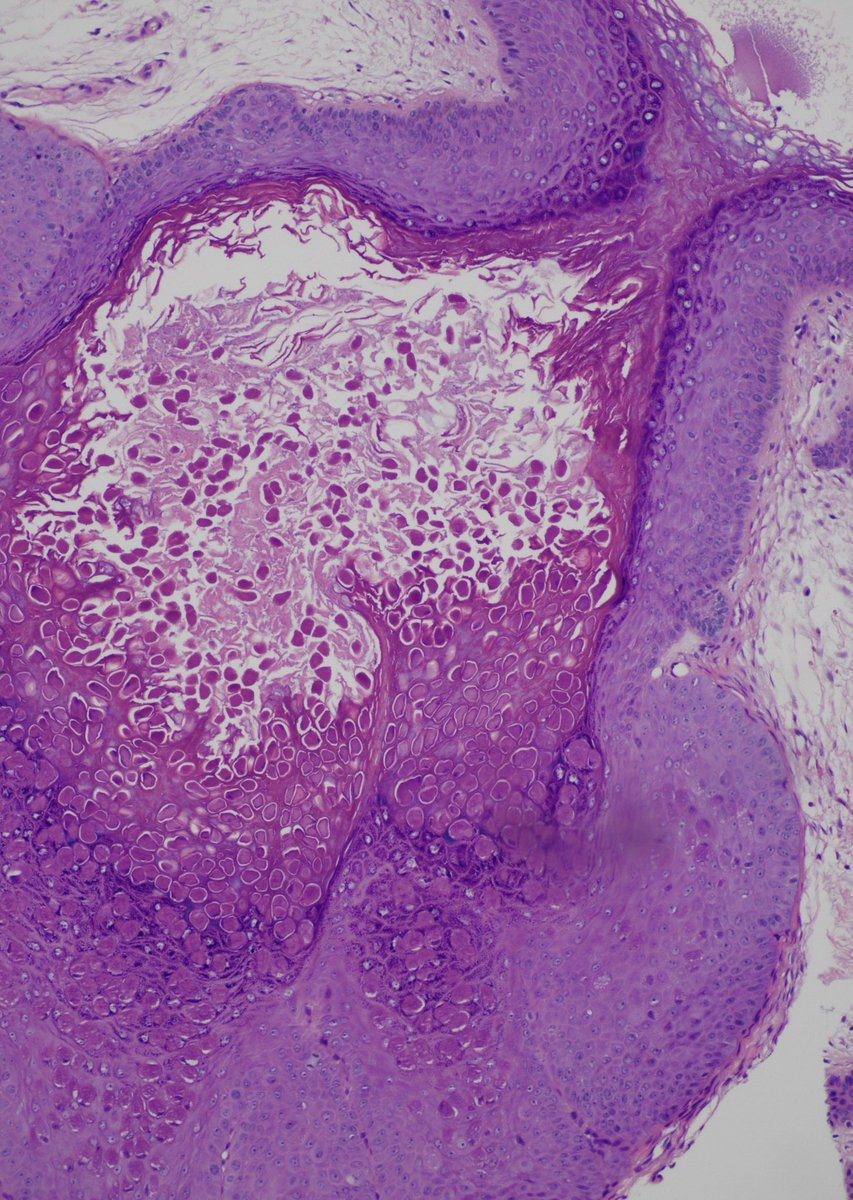

Case from last week. Multiple caecal polyps with plaque- like appearance; rule out malignancy. Nice example of Malakoplakia presenting as caecal polyps.

#gipath#idpath pic.twitter.com/sD8l5wSXMd